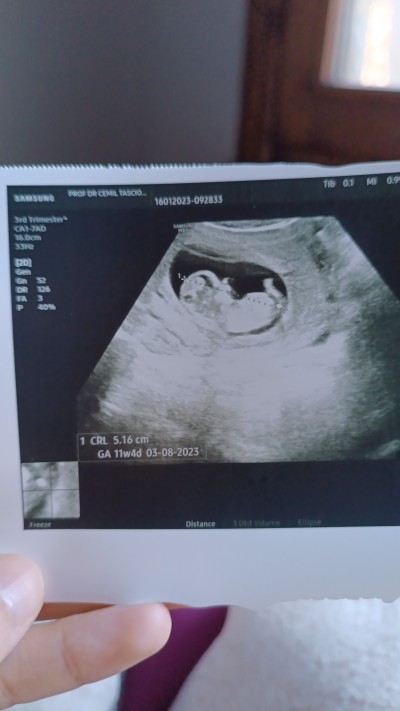

Hanımlar merak ediyorum cinsiyeti ne acaba

image

Gebelik haftası 11